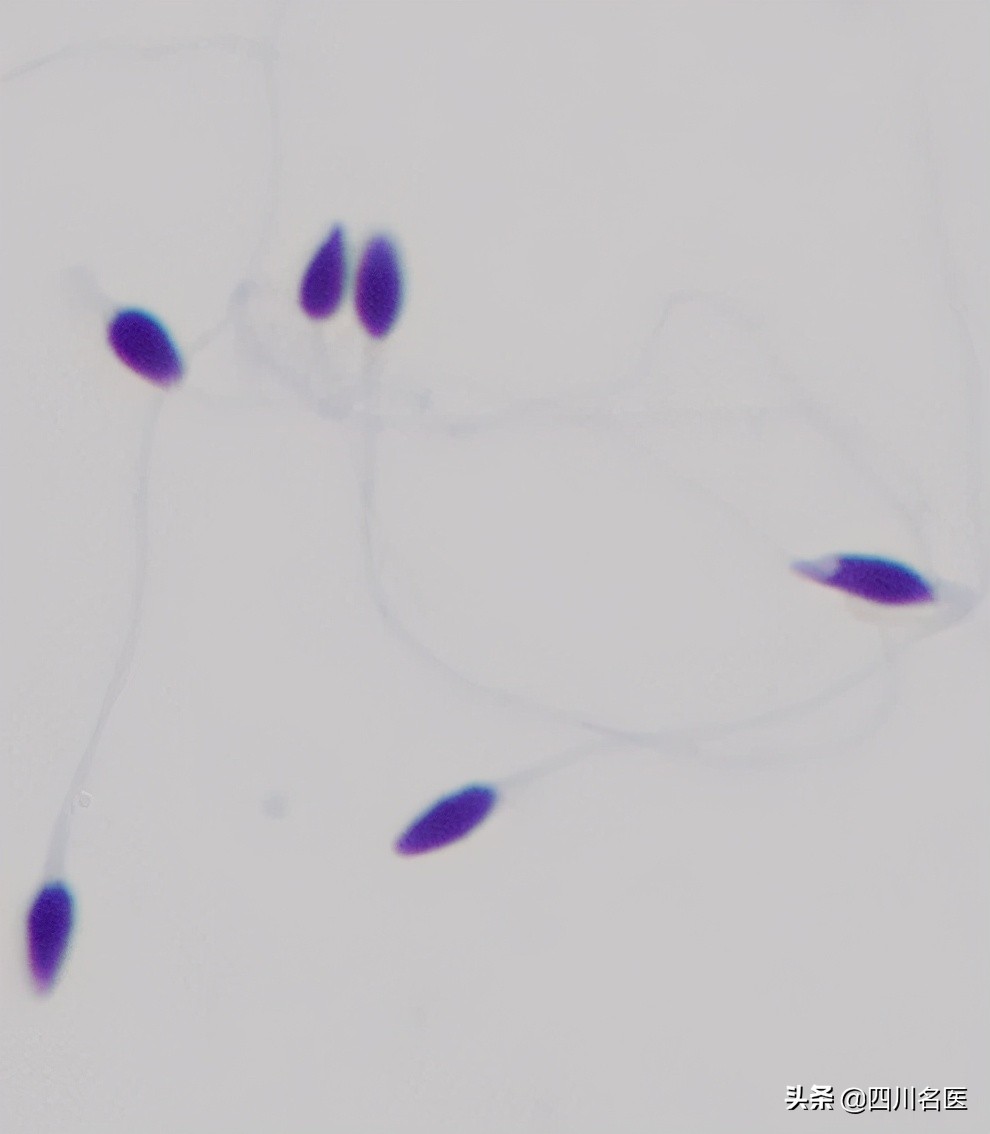

首先,让我们请出本届大赏冠军获得者、精子中的“美人”标杆↓

▲正常形态的精子, 头部大体呈椭圆形,还有一顶“帽子” (顶体)。

▲多头多尾精子

▲锥形头精子

▲精子头部顶体区空泡

▲梨形头精子

02、颈部畸形

▲精子中的“大脖子病” and “歪脖子病”

03、尾部畸形

▲无尾、短尾精子

▲卷尾精子

精子的形态

是精液实验室分析的一个重要指标

通常情况下

只有形态正常的精子

才能完成受精